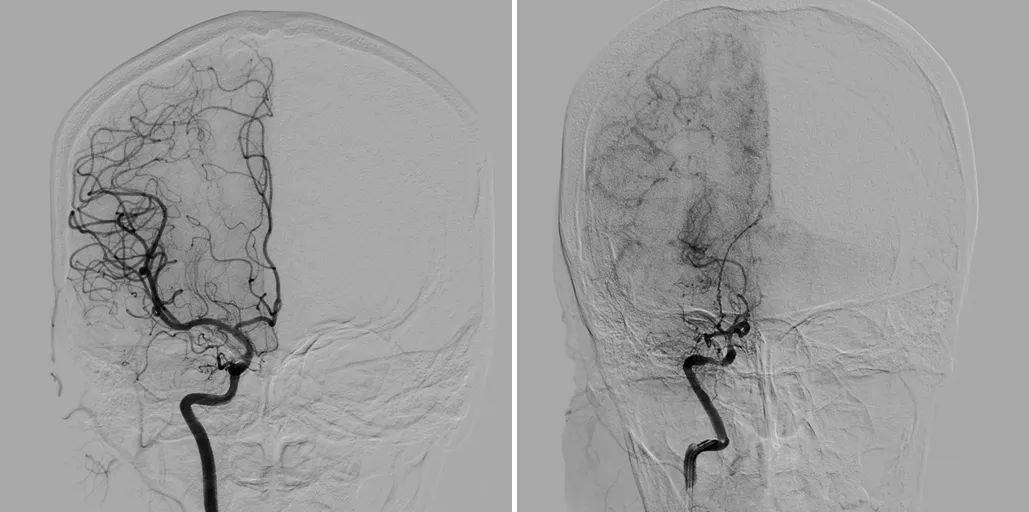

烟雾病(Moyamoya disease)又称自发性基底动脉环闭塞症或脑底异常血管网症,是一种病因不明的慢性脑血管病,是脑部主要动脉(颈内动脉末端及大脑前动脉、大脑中动脉起始部)逐渐狭窄或闭塞,导致脑部供血不足。为了弥补这一缺陷,脑底部会形成异常的细小血管网络,这些血管在脑血管造影中呈现出类似烟雾的影像,因此得名“烟雾病”。

正常血管DSA 烟雾病血管DSA